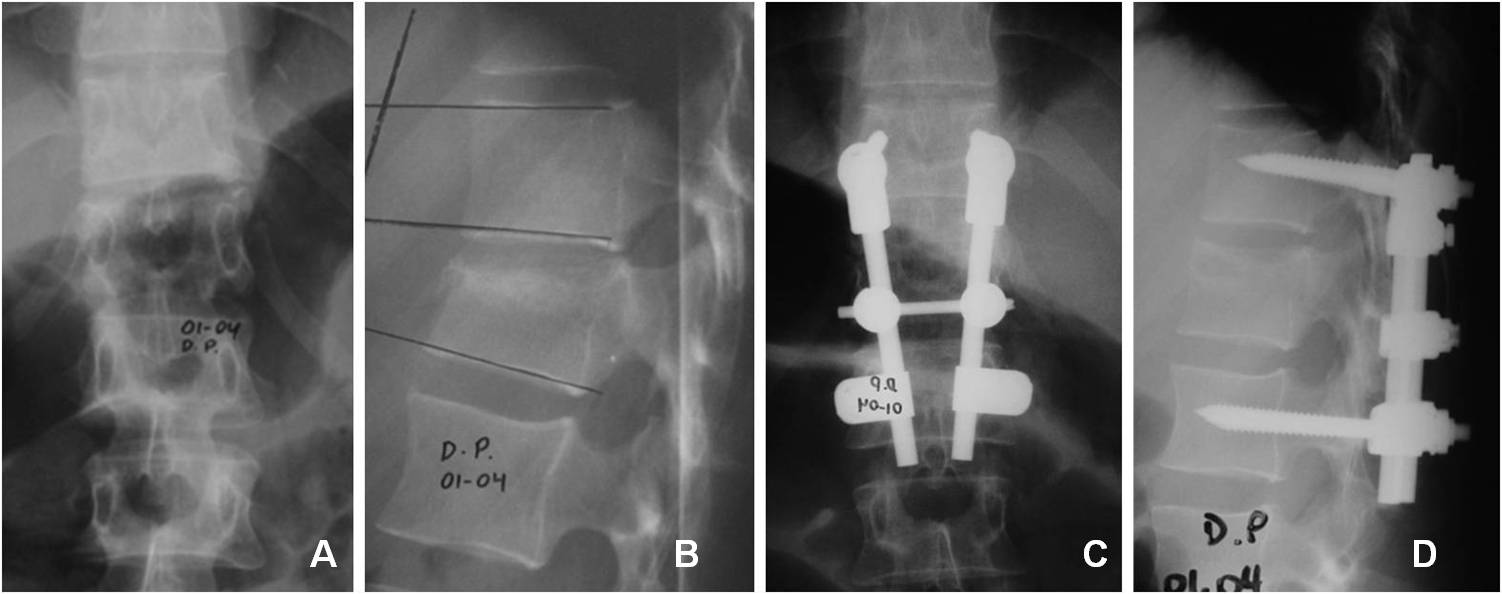

Evaluación clínica y radiológica de la instrumentación y artrodesis corta por vía posterior en fracturas toracolumbares. [Posterior arthrodesis and short instrumentation in thoracolumbar spine fracture:clinical and radiological evaluation]

33. Petracchi M, Gruenberg M, Solá C, Ortolán E. Fracturas por estallido en columna dorsolumbar instrumentadas con tornillos

pediculares. Rev Asoc Arg Ortop Traumatol 2003; 68(4): 273-83.

34. Baños Clemente A, Ramirez Villaescusa J, Martinez Castroverde J, Martinez Arnaiz E, Andreés Gonzalez JM. Tratamiento

quirúrgico de fracturas toracolumbares por vía posterior con instrumentación y fusión bisegmentaria. Rev Esp Traumatol 2002;

37(210):84-88.

35. Parker JW. Successful short-segment instrumentation and fusion of thoracolumbar spine fracture. Spine 2000;25(9):1157-69.